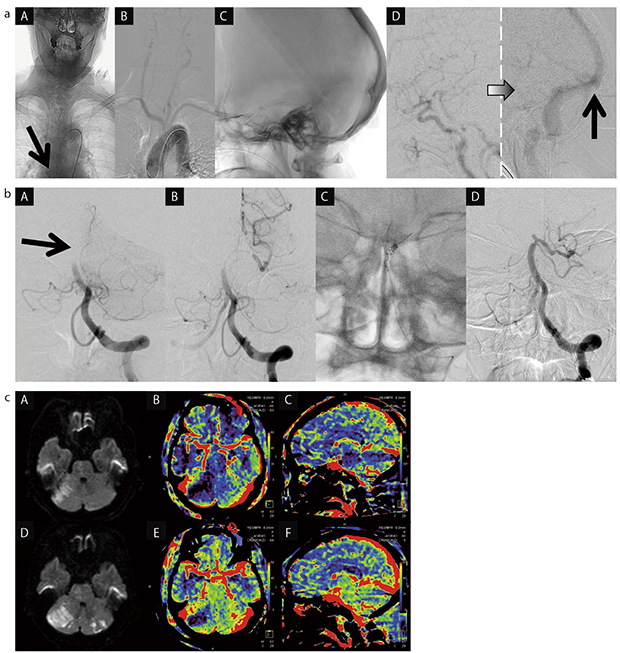

図1 syngo DynaPBV Neuroの臨床使用例

a:テスト撮影。正面視野(A,B)は,48cmの縦長の広い視野に設定し,大動脈弁直上に留置してあるカテーテルの先端(A↓)から頭蓋内までを確認。側面視野(C,D)は,頭蓋内の内頸動脈と静脈洞交会(D↑)が共に確認できる位置に設定(視野はFDサイズによる)。

b:塞栓除去用システムによる血栓除去・再開通療法

c:治療前後のMRIおよびPBVマップ。A〜Cは治療前,D〜Fは治療後。

(画像ご提供:医療法人社団昌医会 葛西昌医会病院脳神経外科・脳血管内治療科様)